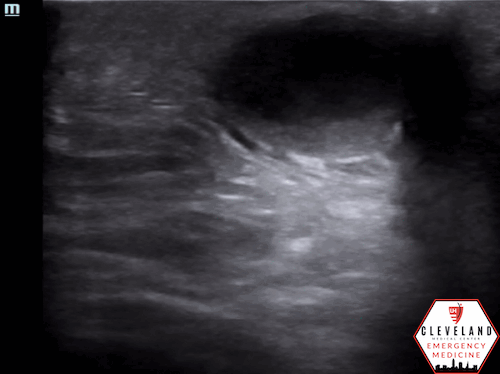

There is a well-circumscribed fluid collection with echogenic debris, consistent with an abscess. Surrounding cobblestoning was also present, supporting concurrent cellulitis in this clinical context. The second lesion demonstrated similar findings of a fluid collection with surrounding cellulitic changes.

• Advanced: hypoechoic fluid tracking between fat lobules, producing the classic cobblestone appearance, as seen in Figure 4 [5].

Figure 4. Late cellulitis with cobblestoning